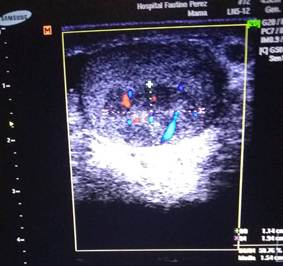

Ecografía Doppler escrotal (Figura 1): informó la presencia de una masa tumoral heterogénea, hipoecoica, localizada en la cara anterior y polo superior del testículo izquierdo, de 10 × 8 mm, con áreas internas quísticas y calcificaciones puntiformes. El estudio Doppler color mostró flujo sanguíneo interno aumentado (hipervascularización), patrón sugestivo de tumor de células germinales (Figura 2). En corte transversal se evidenció el carácter sólido de la lesión, con bordes irregulares y ausencia de sombra acústica posterior (Figura 3).

Figura 1: Ecografía Doppler escrotal, corte longitudinal. Se observa masa heterogénea hipoecoica en polo superior del testículo izquierdo (flecha), con áreas internas quísticas y calcificaciones puntiformes. Diámetro máximo: 10 mm.